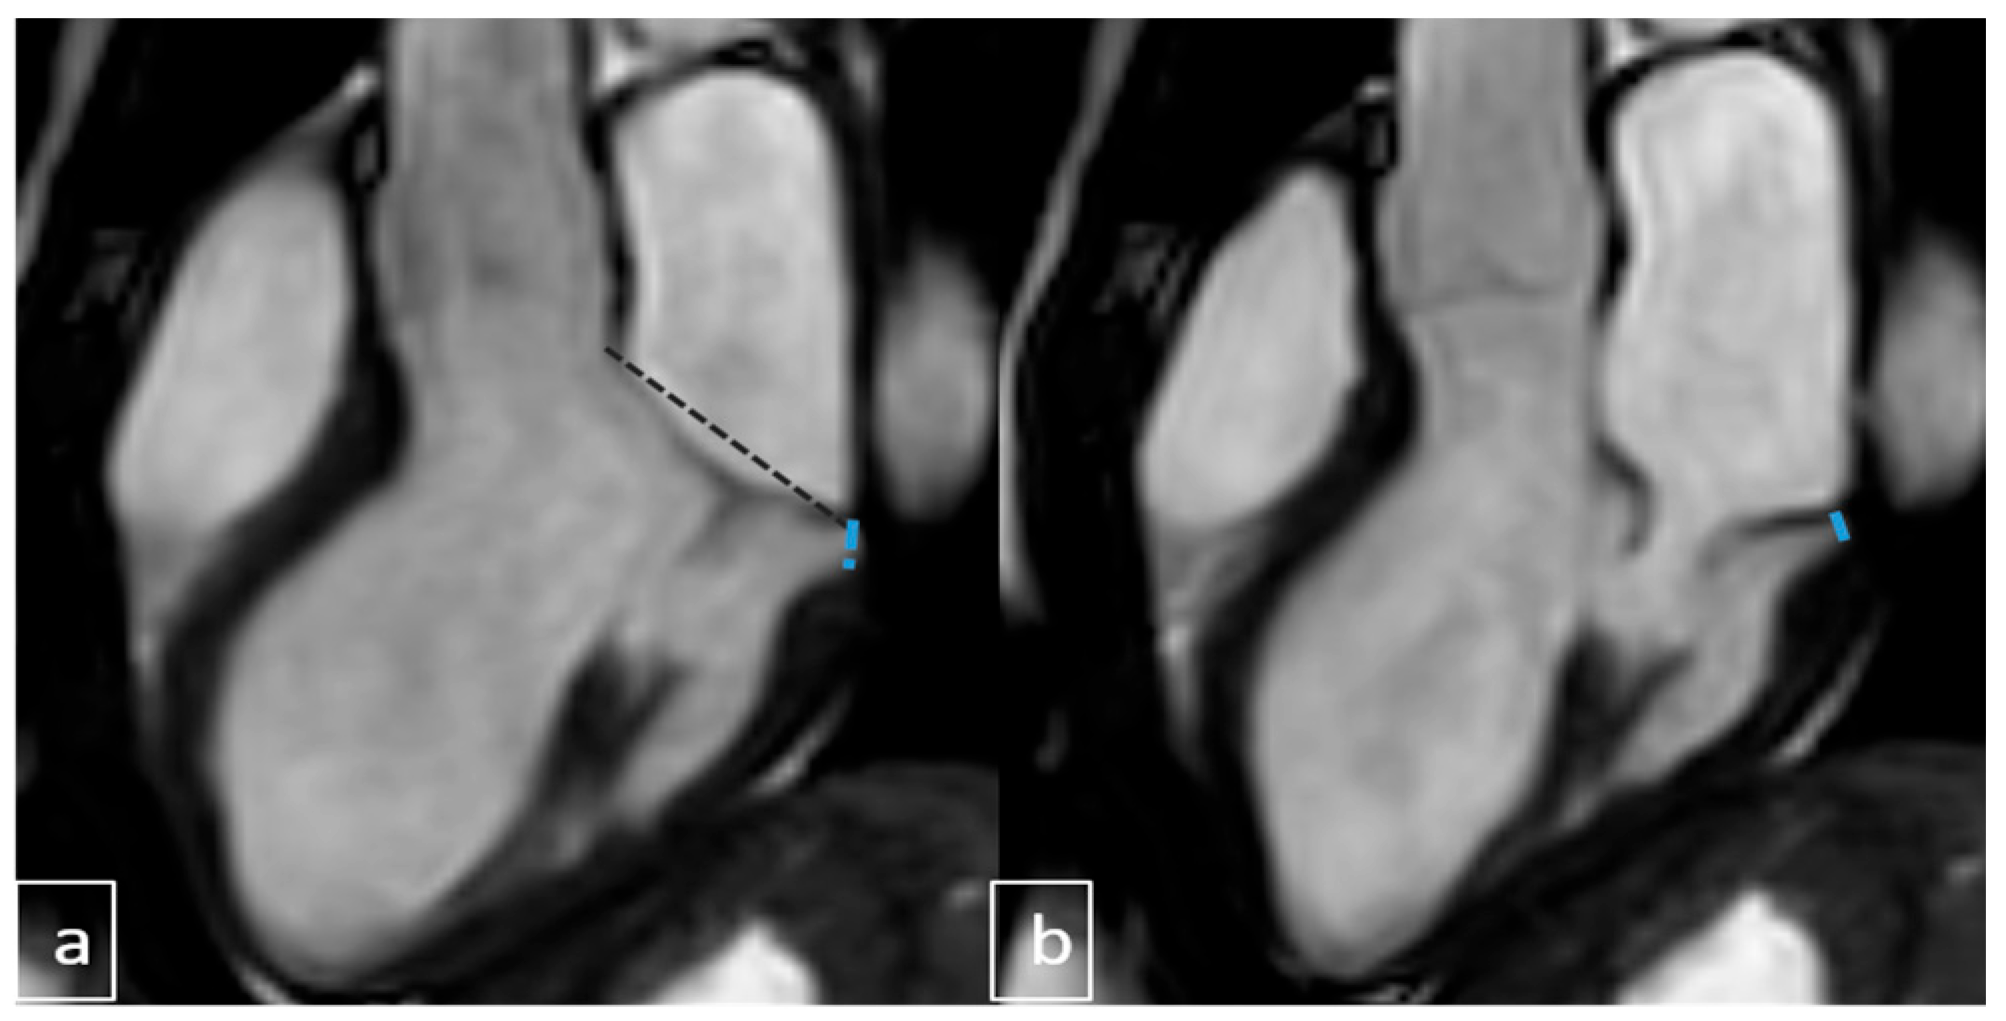

2.4. Image Analysis